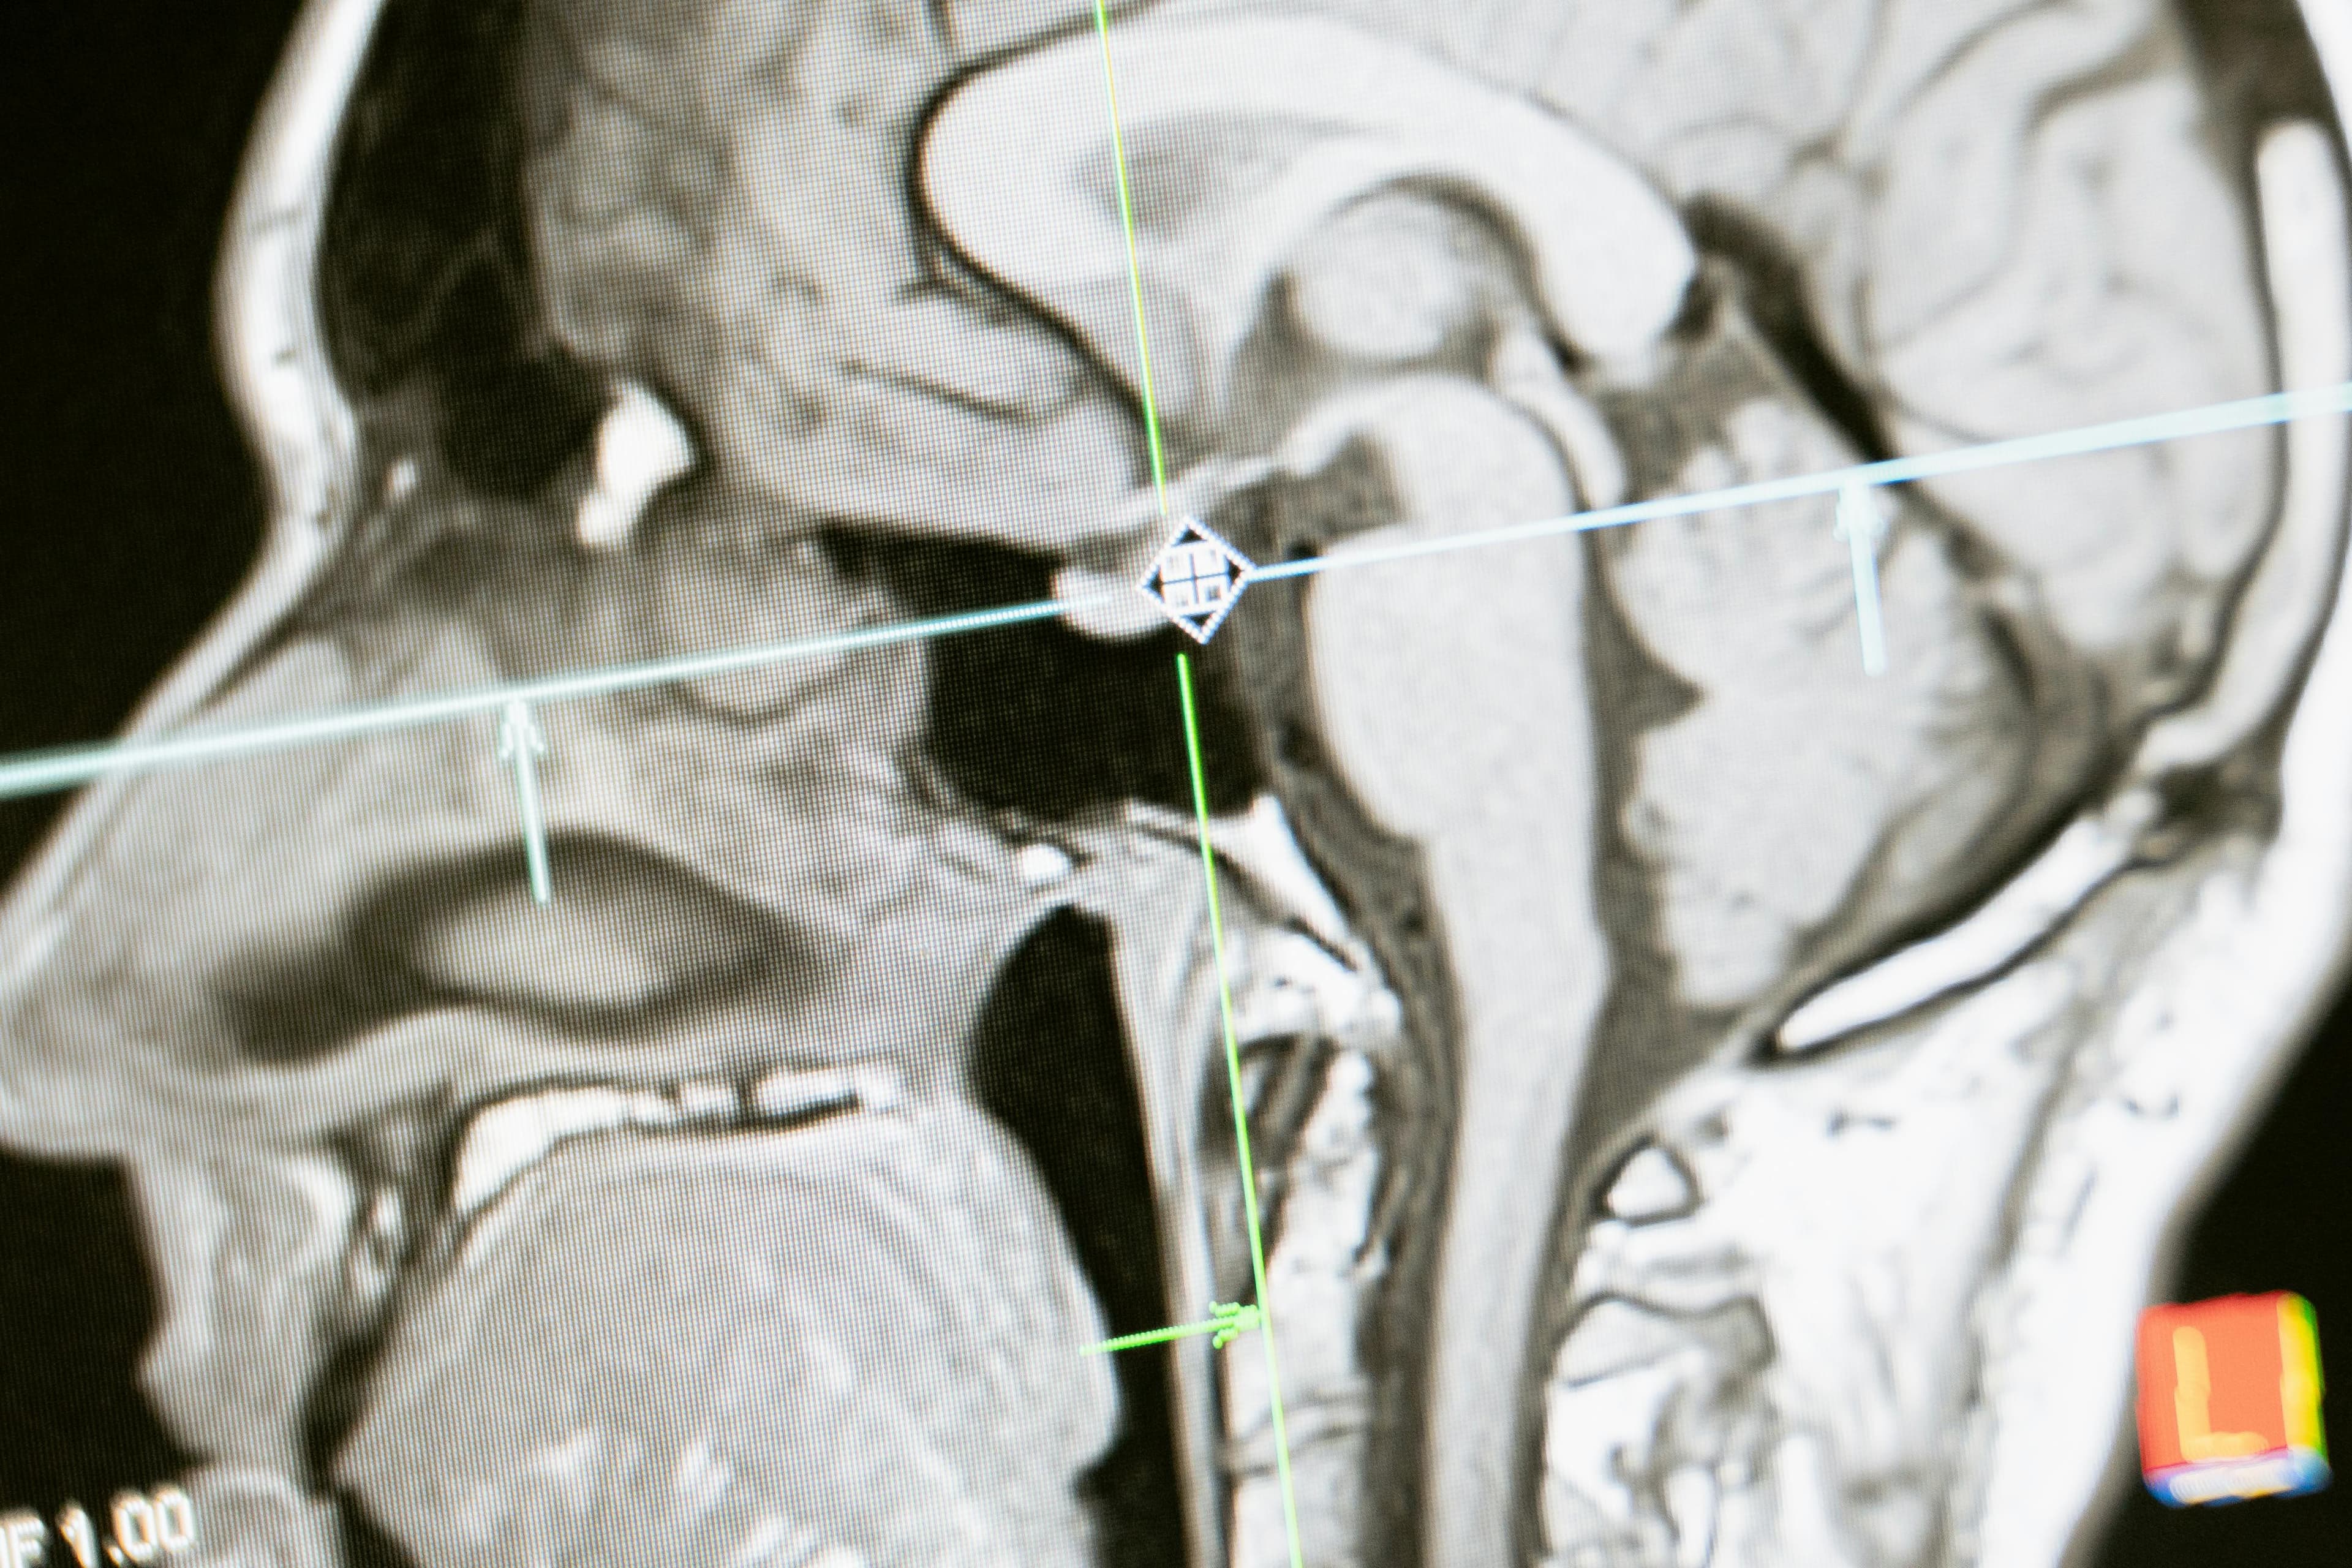

This article focuses on the cognitive and behavioral consequences of brain injuries. It details how Brain Mapping Solutions' advanced neuroimaging technology helps medical professionals link specific brain injuries to behavioral changes, improving diagnosis and treatment outcomes.

Brain Mapping Solutions uses neuroimaging software that links specific brain injuries to cognitive and behavioral deficits, allowing healthcare providers to create targeted treatment plans.

- Advanced imaging that connects injury locations to behavioral outcomes

- Cutting-edge technology for precise cognitive impact analysis

Brain Mapping Solutions offers PRISM Imaging, a state-of-the-art neuroimaging tool that enhances the detection of traumatic brain injuries, seizures, CNS neoplasms, and neurodegenerative diseases.